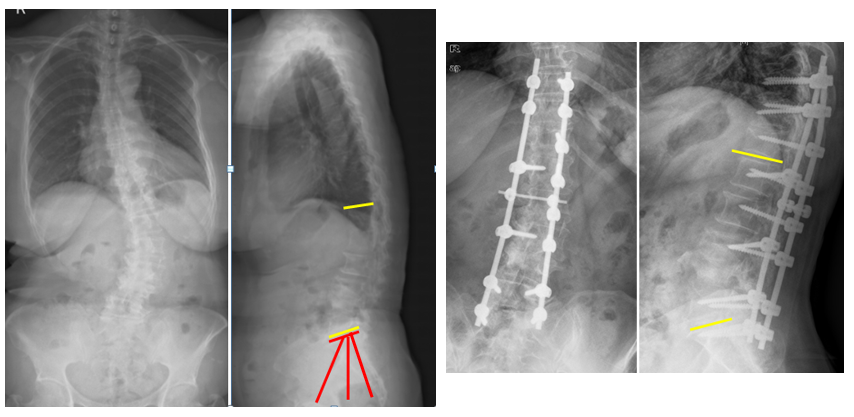

(3)肋骨固定

T10骨盆固定,出现交界性后凸

行翻修手术:T9/10SP截骨,延长到T4固定,预防性双侧肋骨固定(VEPTR)

图32-33 肋骨固定